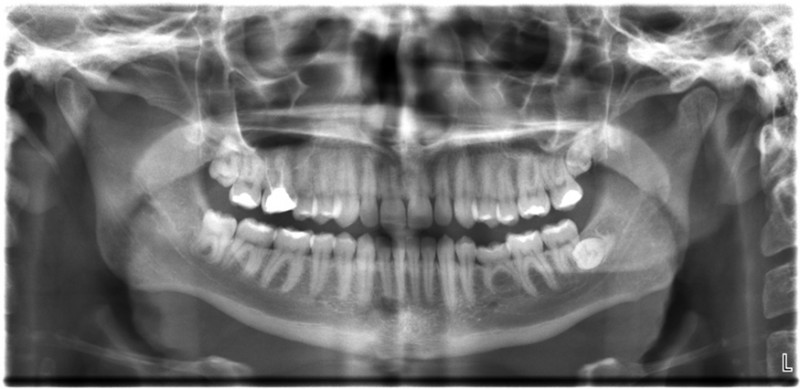

All of us can identify diagnostic uses of x-ray photons. Among these are the universal dental and medical x rays that have become an essential part of medical diagnostics. (See this figure and this figure.) X rays are also used to inspect our luggage at airports, as shown in this figure, and for early detection of cracks in crucial aircraft components. An x ray is not only a noun meaning high-energy photon, it also is an image produced by x rays, and it has been made into a familiar verb—to be x-rayed.

The most common x-ray images are simple shadows. Since x-ray photons have high energies, they penetrate materials that are opaque to visible light. The more energy an x-ray photon has, the more material it will penetrate. So an x-ray tube may be operated at 50.0 kV for a chest x ray, whereas it may need to be operated at 100 kV to examine a broken leg in a cast. The depth of penetration is related to the density of the material as well as to the energy of the photon. The denser the material, the fewer x-ray photons get through and the darker the shadow.

Thus x rays excel at detecting breaks in bones and in imaging other physiological structures, such as some tumors, that differ in density from surrounding material. Because of their high photon energy, x rays produce significant ionization in materials and damage cells in biological organisms. Modern uses minimize exposure to the patient and eliminate exposure to others. Biological effects of x rays will be explored in the next tutorial along with other types of ionizing radiation such as those produced by nuclei.